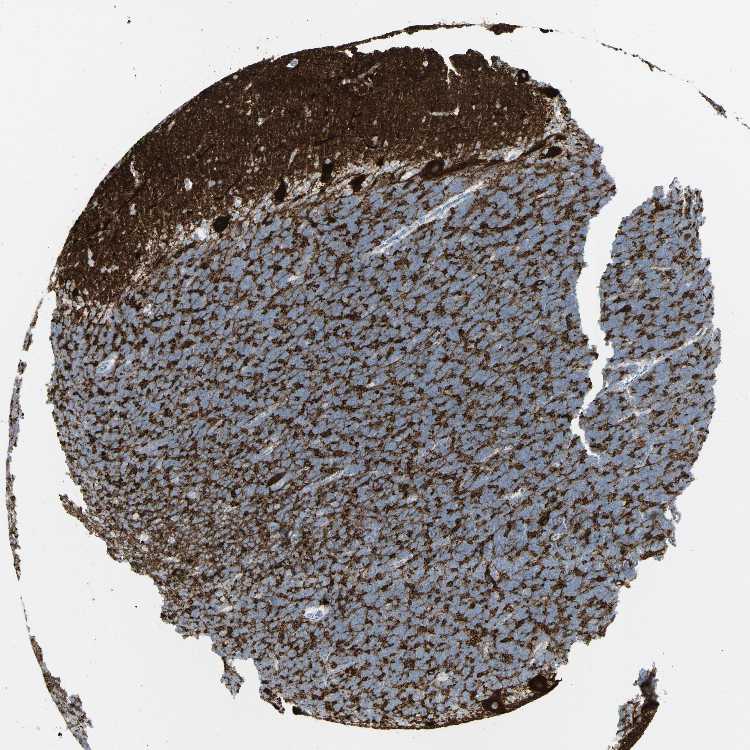

CEREBELLUM - Antibody stainingi

Antibody staining in the annotated cell types in the current human tissue is reported as not detected, low, medium, or high, based on conventional immunohistochemistry profiling in selected tissues. This score is based on the combination of the staining intensity and fraction of stained cells.

Each image is clickable and will lead to virtual microscopy that enables deeper exploration of all samples and also displays staining intensity scores, fraction scores and subcellular localization as well as patient and tissue information for each sample.

Antibody HPA043640Antibody HPA046280Antibody CAB011512

Purkinje cells Not detectedNot detectedHigh

Cells in granular layer Not detectedNot detectedNot detected

Cells in molecular layer Not detectedNot detectedHigh